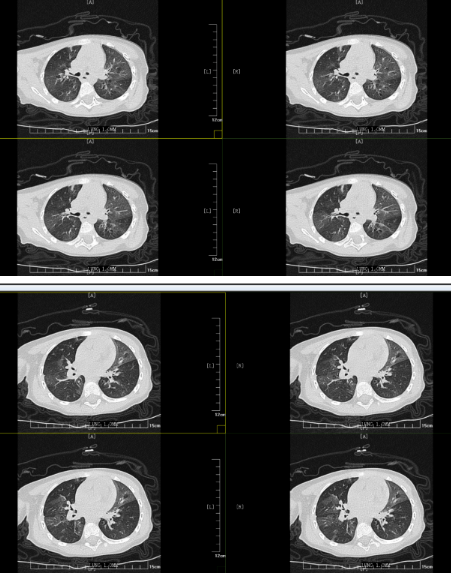

但胸部CT的結(jié)果表明小丸子的肺內(nèi)病變比較重,同時通氣也不均勻,確實存在堵塞,可這個"堵住氣管的東西”到底是什么,還得在支氣管鏡檢查下才能知道。在和小丸子的父母詳細(xì)溝通病情后,入院第二天一早,小兒內(nèi)科田恬主任便為其進行了無痛電子支氣管鏡檢查。